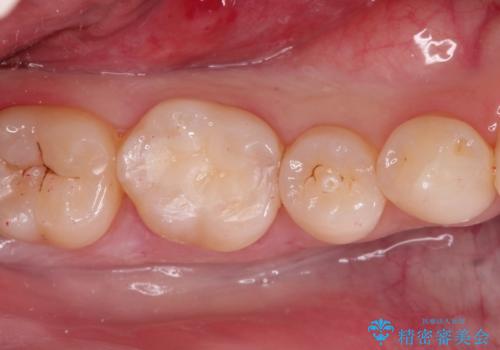

治療では、まず虫歯に侵された歯質を丁寧に除去し、セラミッククラウンを装着するための歯の形成を行いました。型取りから患者様の歯の形や色に合わせたオーダーメイドのセラミッククラウンを作製。セラミックは、隣接する歯との隙間なく精密に適合し、プラークが付着しにくいため、虫歯の再発を防ぐ効果があります。最終的に、精度の高いクラウンを装着し、咬み合わせを細かく調整しました。これにより、虫歯の再発を防ぎ、快適に食事ができる奥歯を取り戻していただけました。